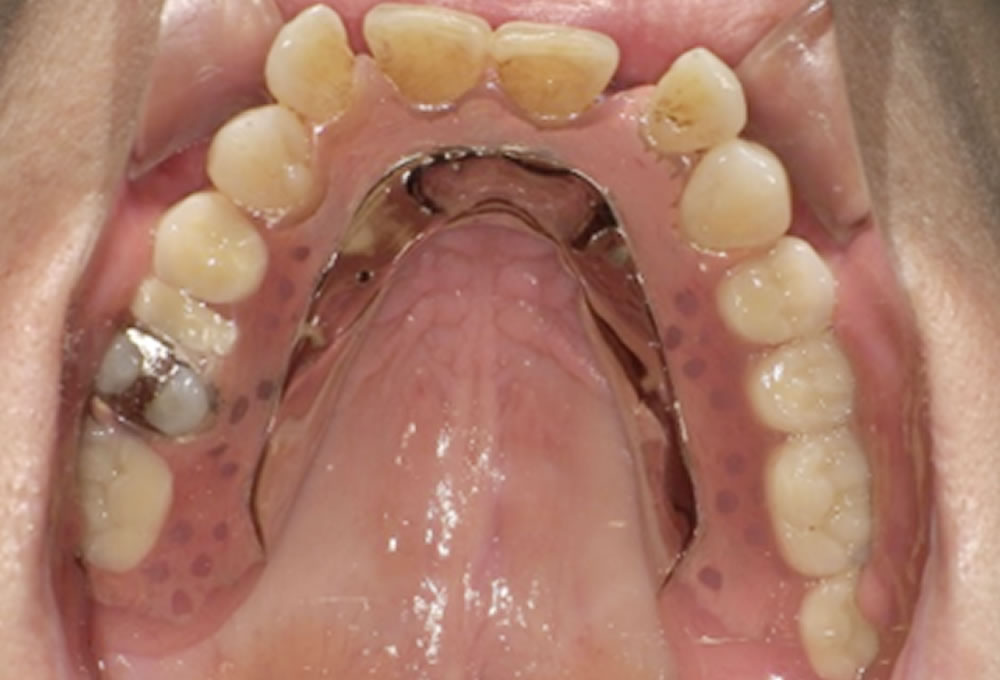

今回採用したのは、現在のお口の状態に柔軟に対応できる設計で、耐久性と審美性の両立が期待できるミラクルデンチャーです。義歯の固定力を高める「ミラクルアルファ加工」を組み合わせた設計となっています。

ミラクルデンチャーは、一般的な入れ歯のように「点」や「線」で歯に負担をかけるのではなく、 残っている歯と“面”で支え合う構造が特徴です。

治療後の変化

治療後は、左右どちらでも安定して噛めるようになり、食事の際の不安が大きく軽減されました。